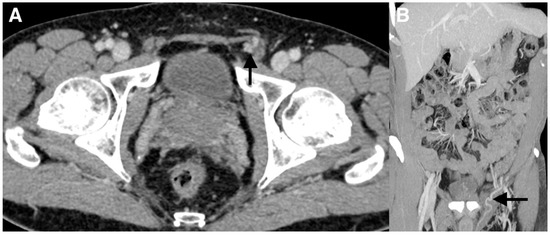

Figure 3. (A) The lack of visualization of the left testicular vein was felt to be due to its possible small caliber; therefore, the patient was scheduled for the antegrade embolization of the left testicular vein. The procedure was performed under local anesthesia. The testicular vein was percutaneously punctured with a 21-gauge metallic needle under ultrasound guidance at the left inguino-scrotal level by direct antegrade approach. A venogram through the needle was performed and demonstrated that the varicocele was supplied by the normal testicular vein (arrow). It was impossible to identify drainage into the left renal at the upper part on the venogram because of the risk of malposition of the needle during contrast injection. One explanation for the failure of the retrograde embolization was the competence of the first testicular vein valve at the level of the renal vein as often described despite the dilation of the testicular vein and the varicocele below. This valve could not be crossed. (B,C) Because of the inability to catheterize deeper the testicular vein with a microcatheter, cyanoacrylate glue embolization was directly performed through the 21-gauge needle. A mixture of Glubran®2 (GEM, Viareggio, Italy) and Lipiodol® (Guerbet, Aulnay-sous-Bois, France) in a 1:1 ratio was gently injected until the occlusion of the two-thirds of the testicular vein above the puncture site and few centimeters below this point (arrow). The catheter was removed and hemostasis was obtained with manual compression. The patient tolerated the procedure and was discharged the same day. He returned to his normal activity without pain and was asymptomatic at the 6 months follow-up. Varicoceles are often mainly treated with percutaneous embolization using fibered coils or sclerotherapy [1]. Coils have the advantage of being easy to use, especially detachable coils. The main drawbacks are the risk of migration if the size is not appropriate and the risk of recanalization, since small collaterals cannot be accurately treated with them. In addition, many coils may be necessary. The limitations of sclerotherapy are: the risk of migration/stroke, allergy, unpredictable diffusion space, total amount limited, inefficient in the case of large varicocele if used alone. The main advantage of sclerotherapy is the very low cost. Liquid embolic agents such as cyanoacrylates are less popular despite many advantages such as lower cost, faster procedure, and a higher capacity of the vein filling, especially collaterals [2]. A deep learning curve is necessary and the choice of low dilution with lipiodol is mandatory to avoid migration in the case of reflux. The entrapment of the microcatheter is exceptional in clinical practice if embolization is performed properly. There are not only a few cases with percutaneous antegrade varicocele embolization via the testicular vein at the level of the pubis, but also no reports of cyanoacrylate glue embolization in such a setting as we herein described [3,4].